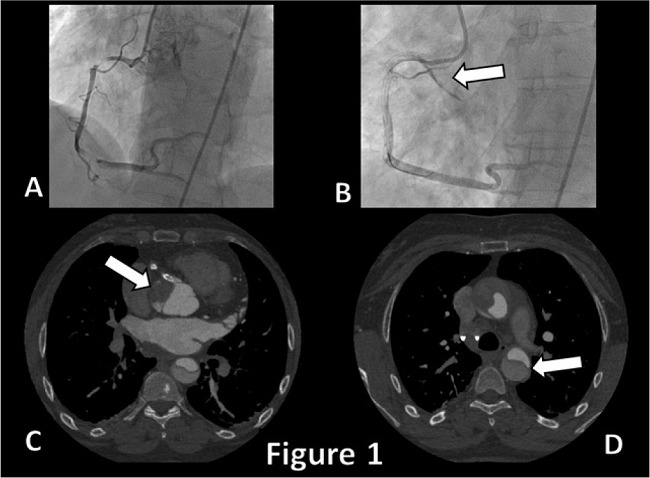

During the procedure, a dissection of the RCA with the subsequent development of an aortic wall hematoma was detected at fluoroscopy; such hematoma quickly extended in a retrograde fashion (Video 1) from the right sinus of Valsalva up to the ascending aorta (Figure 1). An attempt to occlude the intimal entry orifice was made by delivering a right ostial stent, but, unfortunately, the dissection progressed towards the aortic arch, so an emergency surgery was required.